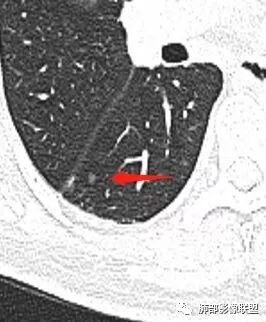

马宁强:考虑肉芽肿性病变,隐球菌可能彭君:左肺上叶舌段混合毛玻璃密度结节 边缘清 有分叶毛刺 斜裂胸膜凹陷征 考虑腺癌可能王秀仙:左肺上叶结节,部分边缘磨玻璃清晰,有分叶毛刺,支气管通过并扩张,其外侧小叶间隔不规则增厚,胸膜牵拉,考虑腺癌。鉴别慢性炎症。田园晚风:左肺上叶多个小结节融合呈分叶状,可见叶间裂牵拉,考虑腺癌张帅:左肺上叶后段结节,内可见支气管穿过,病灶周围有少许毛刺,病灶边缘有浅分叶,对叶间胸膜有牵拉,部分位置呈对叶间胸膜推移。考虑为恶性病变,腺癌?。杨泽锋:混合型磨玻璃结节,边缘有膨隆、有凹陷,明显的胸膜牵拉,考虑腺癌可能大;内部支气管通畅、似乎有鬼脸征,所以鉴别隐球菌Lotus:病灶内部有结节感,这个大小似乎是次级肺小叶的大小,考虑炎性,有冠位最好了。但是胸膜牵拉有些恶性提示心包右侧软组织密度影考虑心包隐窝Yiren Sishui(厶水伊人):叶间裂有膨隆有凹陷,考虑恶性,腺癌可能

徐婕:同意恶性腺癌可能岁月:女,56;空泡,分叶毛刺,牵拉线,胸膜凹陷征,有强化,浸润性腺癌。THINKER:左舌见结节,膨胀为主,部分收缩,分叶丶短丶硬毛刺,牵拉斜裂,有小空泡,支气管穿行,有强化,常规腺癌丽:左肺上叶近胸膜下结节,胸膜牵拉,边缘膨隆,并可见深分叶及毛刺,内有空泡,增强后可见强化,倾向腺癌淘时光:混合磨玻璃结节,实性部分较多,内见支气管穿行,腺癌首先考虑了…☀:左肺上叶结节影,实性,边缘分叶征,其内可见空泡,部分膨胀生长,局部叶间裂牵拉上移,叶间裂光滑增厚,首先考虑肿瘤黄棘:左肺上叶结节,边缘彭隆, 周围磨玻璃影边界清,内部可见扩张支气管,叶间胸膜牵拉,考虑腺癌心灵鸡汤:左肺上叶舌段近斜裂处混合性结节,以实性成分为主,有分叶、毛刺,牵拉邻近叶间、脏层胸膜,增强有强化,影像学上看偏恶性,分类LU-RADS 4C类,MIA浸润性腺癌可能,鉴别肉芽肿性病变、隐球菌,请老师指点!THINKER:这个如果是腺癌,应该是IAC了,过MIA了,个人看法,罗老师一切∮随缘:左肺叶裂胸膜下结节,边缘收缩弱,周围有GGO,边界清楚,形态欠规则,其内似有支气管穿行,增强扫描轻度均匀强化,考虑1肉芽肿性病变(隐球,炎性假瘤)2:浸润性腺癌Clover:考虑腺癌,实性为主混合有少许边界清晰ggo,边缘膨隆,其内支气管气象不规则,有收缩力。Coke with ice:还有一个疑问请教一下:这个是混合磨玻璃结节还是实性结节?个人倾向于后者。心灵鸡汤:有部分磨玻璃Coke with ice:实性结节周围GGO初学者:实性,周围有毛玻璃晨:有浅分叶,有毛刺,有叶间裂牵拉,内有囊泡,考虑腺癌。初学者:稍等,我等会开电脑看,但是感觉和你们一样,感觉是一个典型病例来着Coke with ice:这个人我也倾向于腺癌。但是诊断腺癌还有一个比较疑惑的地方,肺窗病变密度显示比较实,但是纵隔窗病灶范围明显比肺窗小,腺癌可以解释的通吗?张小兵:混合磨玻璃结节,内见支气管穿行,分叶,胸膜牵拉从凹陷处进入,腺癌首先考虑小微:

看看这个。左边为什么会胸膜往上?因为左边是GGO为主,右边是比较实,就占位效应出来,所以凸出来了心灵鸡汤:@岳微-辽宁省朝阳234医院-影像诊断 应该是心包隐窝初学者:如是炎症,是同步发生,首先边缘不会有边界清楚的GGO,慢性炎症应该连渗出都很少了,更加不会有一部分是收缩,一部分是膨隆

南边:有边界清楚GGO吗张玉:有南边:有就好办边界清楚MGGO,分叶、胸膜凹陷